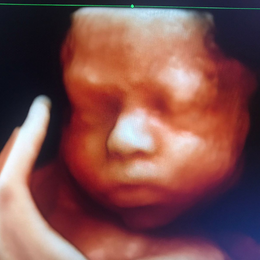

Ecografía del corazón fetal en 4D

- Las formas nuevas de ecografía pueden proporcionar imágenes en 5-D.